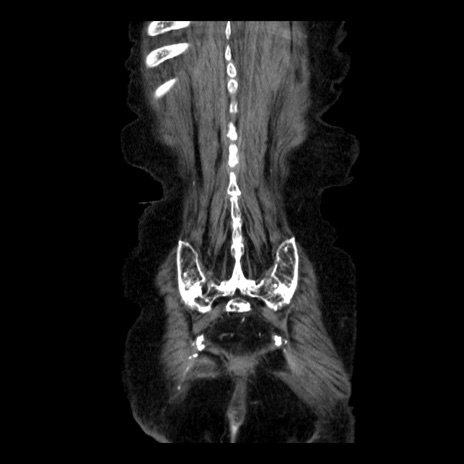

症例14(冠状断像)

【症例】 90歳代女性

【主訴】 腹痛・嘔吐

【現病歴】今朝から左側腹部痛を認めた。 経過観察していたが、嘔吐を認めたため来院。

【既往歴】 子宮癌術後

【身体所見】 意識清明、BP 127/54mmHg、P 98bpm Sp02 95%(RA)、BT 35.8°C、腹部平坦・軟腸ぜん動音聴取良好、右下腹部圧痛(+) 反跳痛なし

【データ】WBC 9800、CRP 0.46